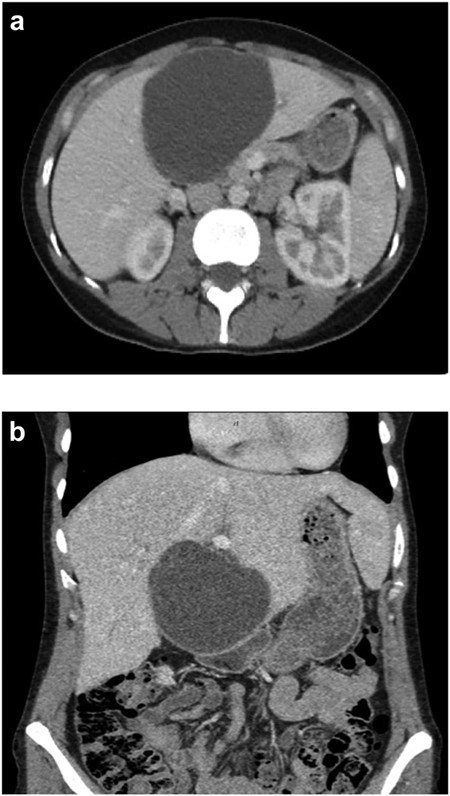

(a) Axial CT abdomen of a septated 10 × 7 cm cystic liver neoplasm. (b) Coronal CT abdomen of a duodenal obstruction secondary to a liver mass.

A 35-year-old female with a medical history significant for acute biliary pancreatitis status post laparoscopic cholecystectomy, presented to the surgery clinic as a new consult for a large cystic liver mass with increasing abdominal pain for 2 weeks. Patient reported suffering from severe pain in right chest, shoulder and diffuse abdominally that worsened with standing. Patient complained of inability to inspire due to pain and a 10-pound weight gain over 2 months. She confirmed decreased appetite especially with solids, nausea and emesis, alternating constipation and diarrhea, bruising, and pruritus at night. Computed tomography (CT) scan demonstrated a peripherally septated 10 x 7 cm cystic mass in the liver with intrahepatic biliary dilation (Fig. 1). The patient was referred for endoscopic retrograde cholangiopancreatography (ERCP) to establish preoperative biliary anatomy and was found to have moderate compression of the common hepatic duct managed with a right hepatic biliary endoprosthesis (Fig. 2); no obvious communication of the biliary tree with the cystic lesion was seen. Patient symptoms persisted despite optimizing with a protein-rich liquid diet; thus, the decision was made to proceed with the surgical plan for an open partial central hepatectomy. The patient was taken to the operative theater. After induction of general anesthetic, an upper midline incision was made. Inspection of the abdomen and liver showed no metastatic lesions grossly or with ultrasonographic imaging. The cyst was visible upon entry into the abdomen with no solid component to the mass in proximity to the cystic neoplasm. The second portion of the duodenum was adherent to the cyst with inflammatory adhesions and was quite boggy. A partial central hepatectomy was performed; a 3 mm biliary duct was found communicating to the cyst only with no drainage to the minimal liver parenchyma that was removed (Fig. 3). The cyst was resected en-bloc and was sent for permanent section (Fig. 4), which diagnosed the tumor as a low-grade mucinous cystic neoplasm measuring 8.5 × 7.2 × 6.4 cm. Microscopy revealed a smooth-walled, multiloculated cyst filled with a yellow-golden, semi-transparent and mucinous fluid (Fig. 5a–c). The cyst was lined by a mucinous epithelium with ovarian-type stroma. No high-grade dysplasia or malignancy was identified. The postoperative course was uneventful, and the patient was discharged on postoperative day 6. At the 4-week postoperative visit, the patient was healing well with some incisional soreness; patient was seen for removal of her biliary endoprosthesis, and ERCP found left sided intrahepatic duct biliary dilatation including a small biliary fistula from the left system (Fig. 6) with the appearance of torque on the extrahepatic biliary tree. A biliary endoprosthesis was left in place, and the patient returned for repeat ERCP 4 weeks later with resolution of all findings (Fig. 7). At present, patient remains alive with no signs of recurrence.